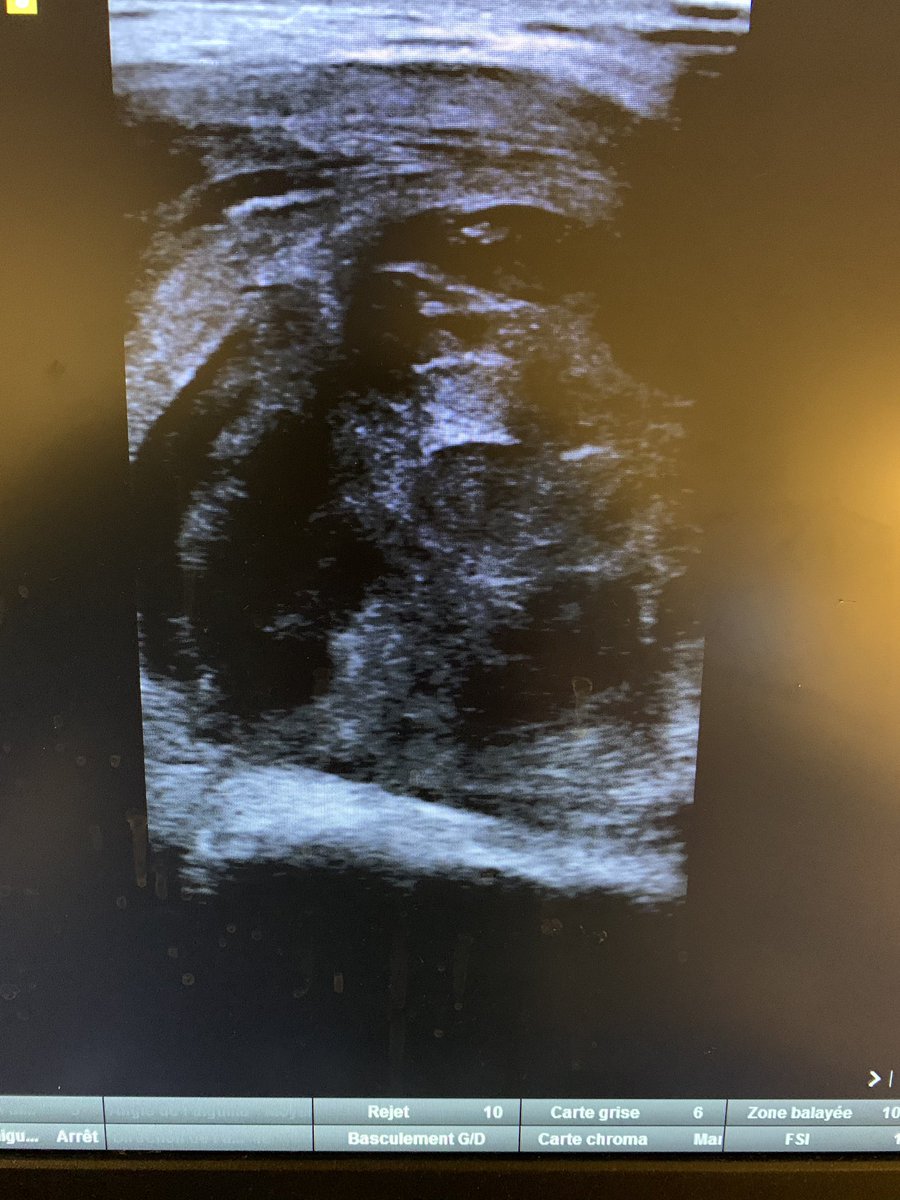

H, 30a, consulte pour douleurs au bras gauche suite à une rixe avec plaie par tournevis il y a 1 mois.

Cliniquement : masse indurée en regard du biceps.

Il consulte devant la persistance de douleurs aux Urgences.

Je découvre plus haut, une brèche dans l’artère huméral, avec la formation d’un pseudo-anévrysme à très haut débit, responsable probablement de ce gros hématome.